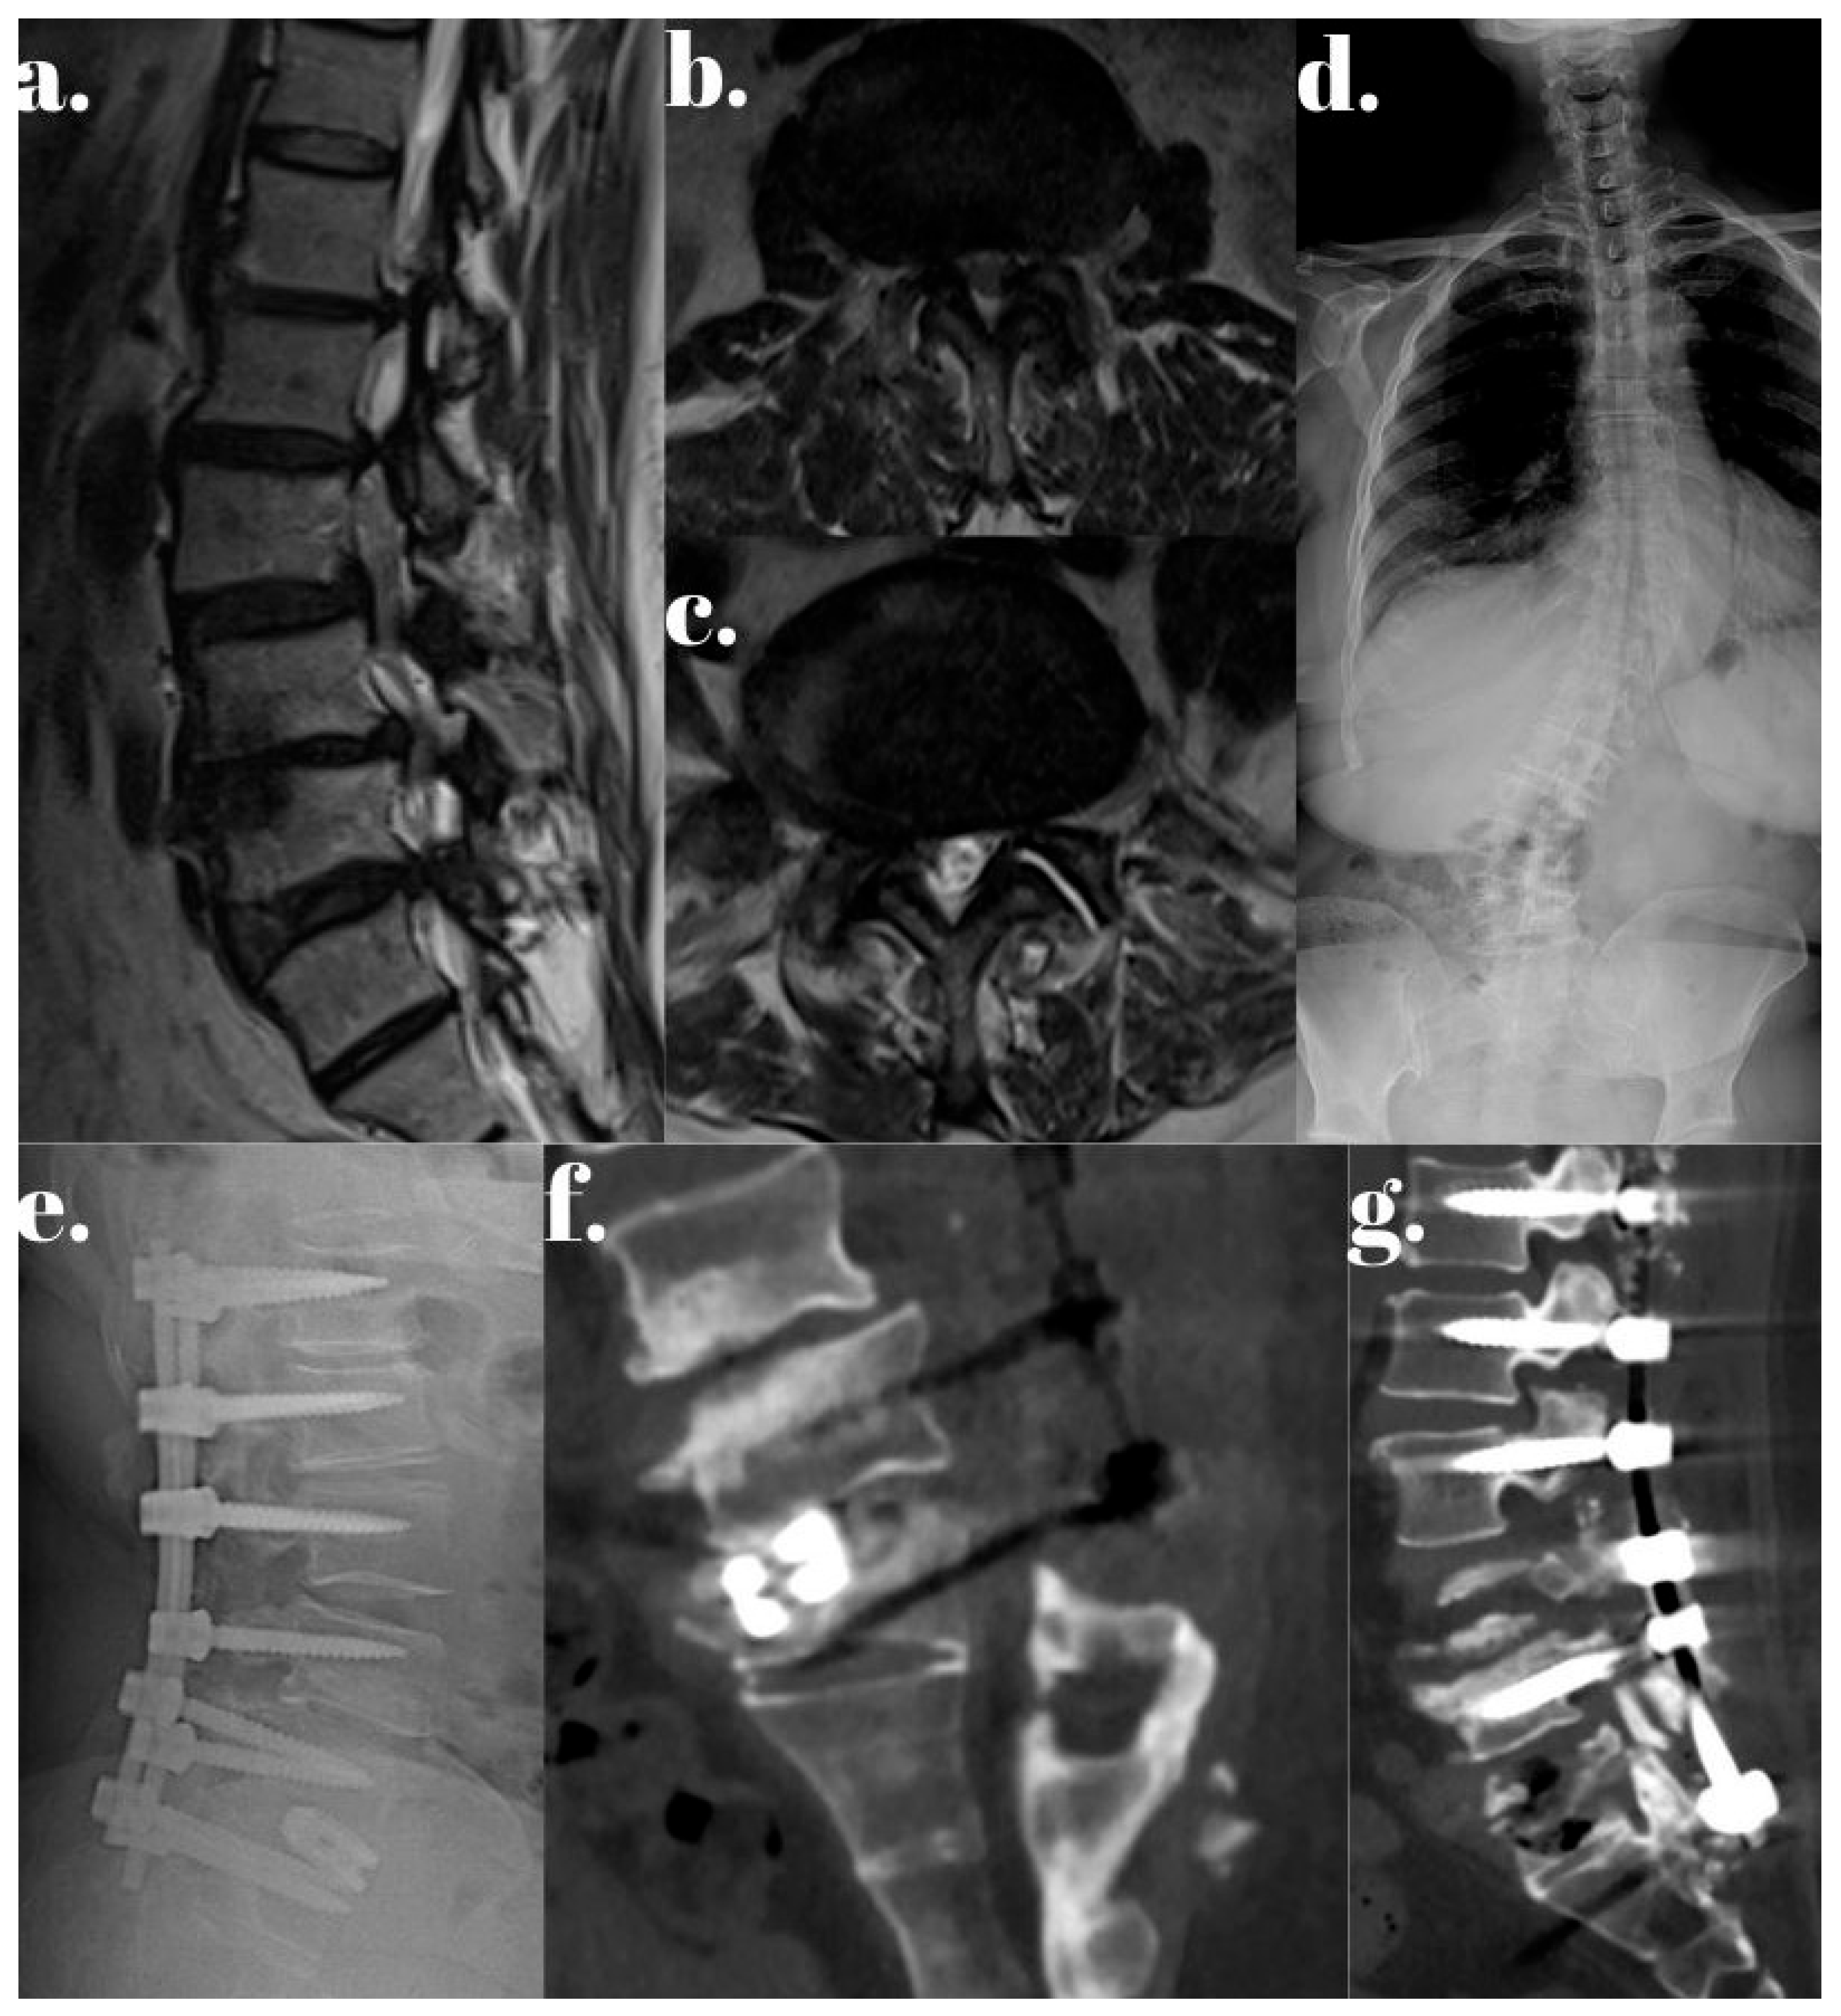

- Özer, A.F.; Başak, A.T.; Özbek, M.A.; Hekimoğlu, M.; Aydın, A.L.; Ateş, Ö.; Günerbüyük, C.; Akgül, T.; Sasani, M.; Öktenoğlu, T. Lumbar Dynamic Stabilization with 2-Stage Surgery: Early Results. Int. J. Spine Surg. 2022, 16, 638–645. [Google Scholar] [CrossRef]